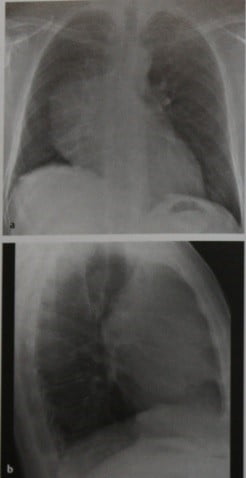

Тимомегалия: что это такое и как проявляется